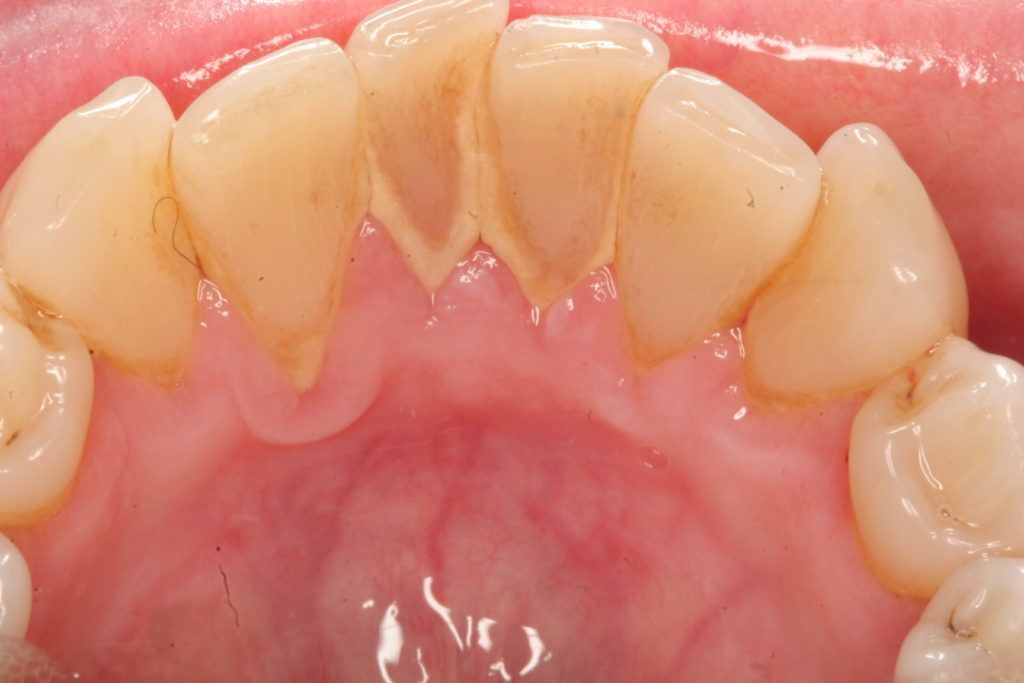

Cao răng, hay còn gọi là vôi răng hình thành bên dưới hoặc bên trên phần rìa lợi. Cao răng có bề mặt thô ráp, rỗ và có thể làm tụt lợi và bệnh về lợi. Việc loại bỏ cao răng cần dùng đến các dụng cụ đặc biệt tại phòng khám nha khoa.

Cao răng có thể khiến việc đánh răng và dùng chỉ nha khoa trở nên khó khăn hơn. Điều này sẽ dẫn đến sâu răng và thủng răng.

Cao răng khi hình thành bên trong lợi sẽ đặc biệt có hại bởi vì vi khuẩn có trong cao răng có thể gây kích ứng và làm tổn thương đến lợi. Theo thời gian, điều này sẽ dẫn đến bệnh về lợi kéo dài.